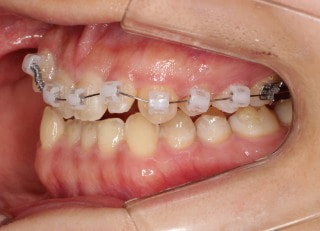

治療後(2年11ヶ月後)

治療開始から25ヶ月後